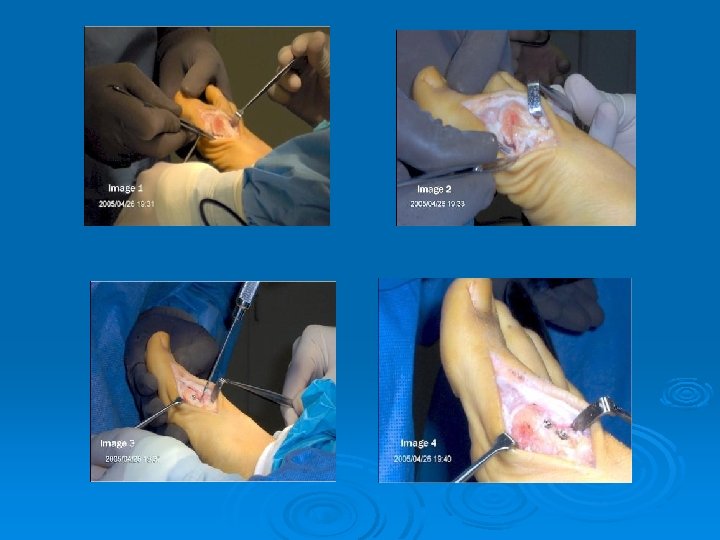

Ingrown Toenail Ø MX: l Improper shoe fitting and nail cutting Ø S/S: l Increased pain, swelling, redness around the nail bed Ø TX: l Hot, soapy water, antibiotics, raise nail up Ø Prevention: l Proper shoes, proper nail trimming